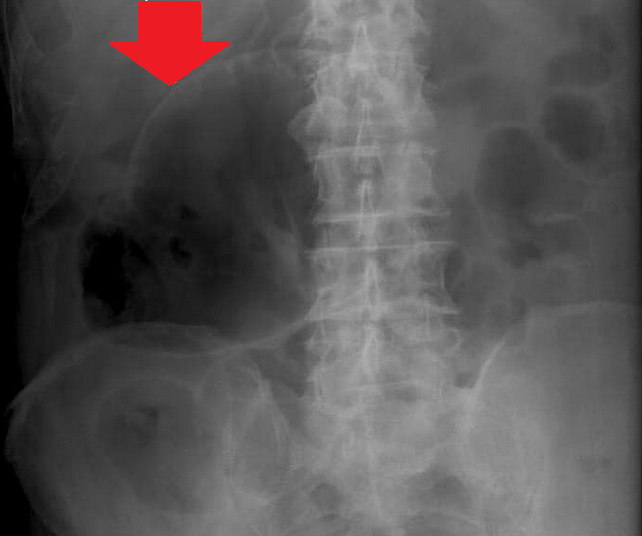

Παρουσία αέρα στο πυλαίο φλεβικό σύστημα, δευτεροπαθώς σε ισχαιμική κολίτιδα (Ευγενική παραχώρηση Dr. V. Penopoulos)